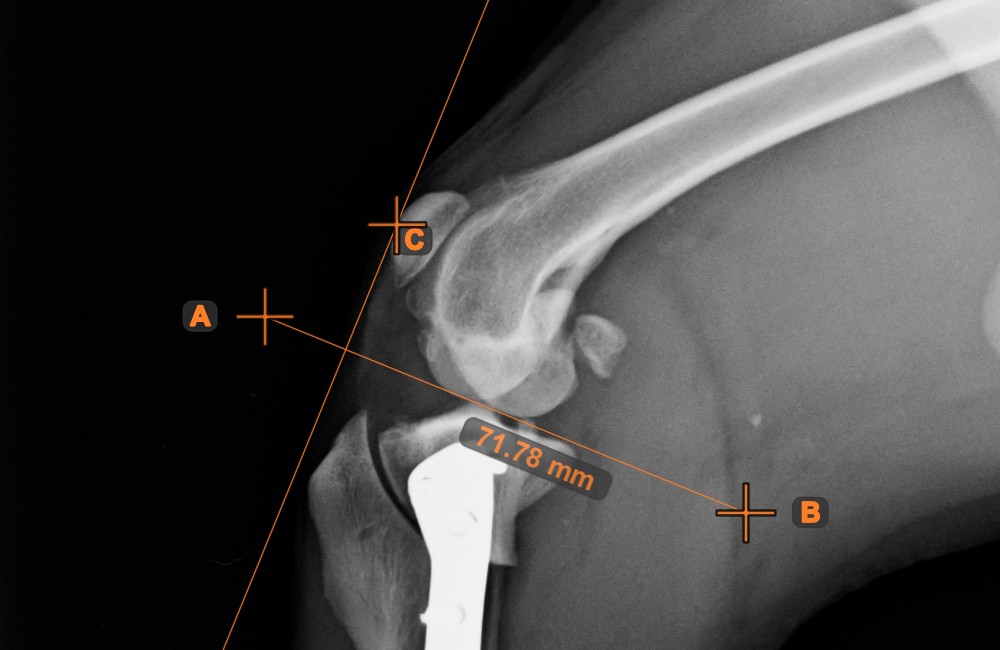

Line Measurement¶

Select the Line Measurement tool and assign it to one of the available mouse buttons. Place the start and end points on the scene or select them from already existing points on the image. The distance between the two points will be automatically

calculated by using the default calibration data, or the recalibrated data by the length calibration measurement.

Modify the start and end point by using the Select/Move Item tool. The distance between the two points will be automatically recalculated.